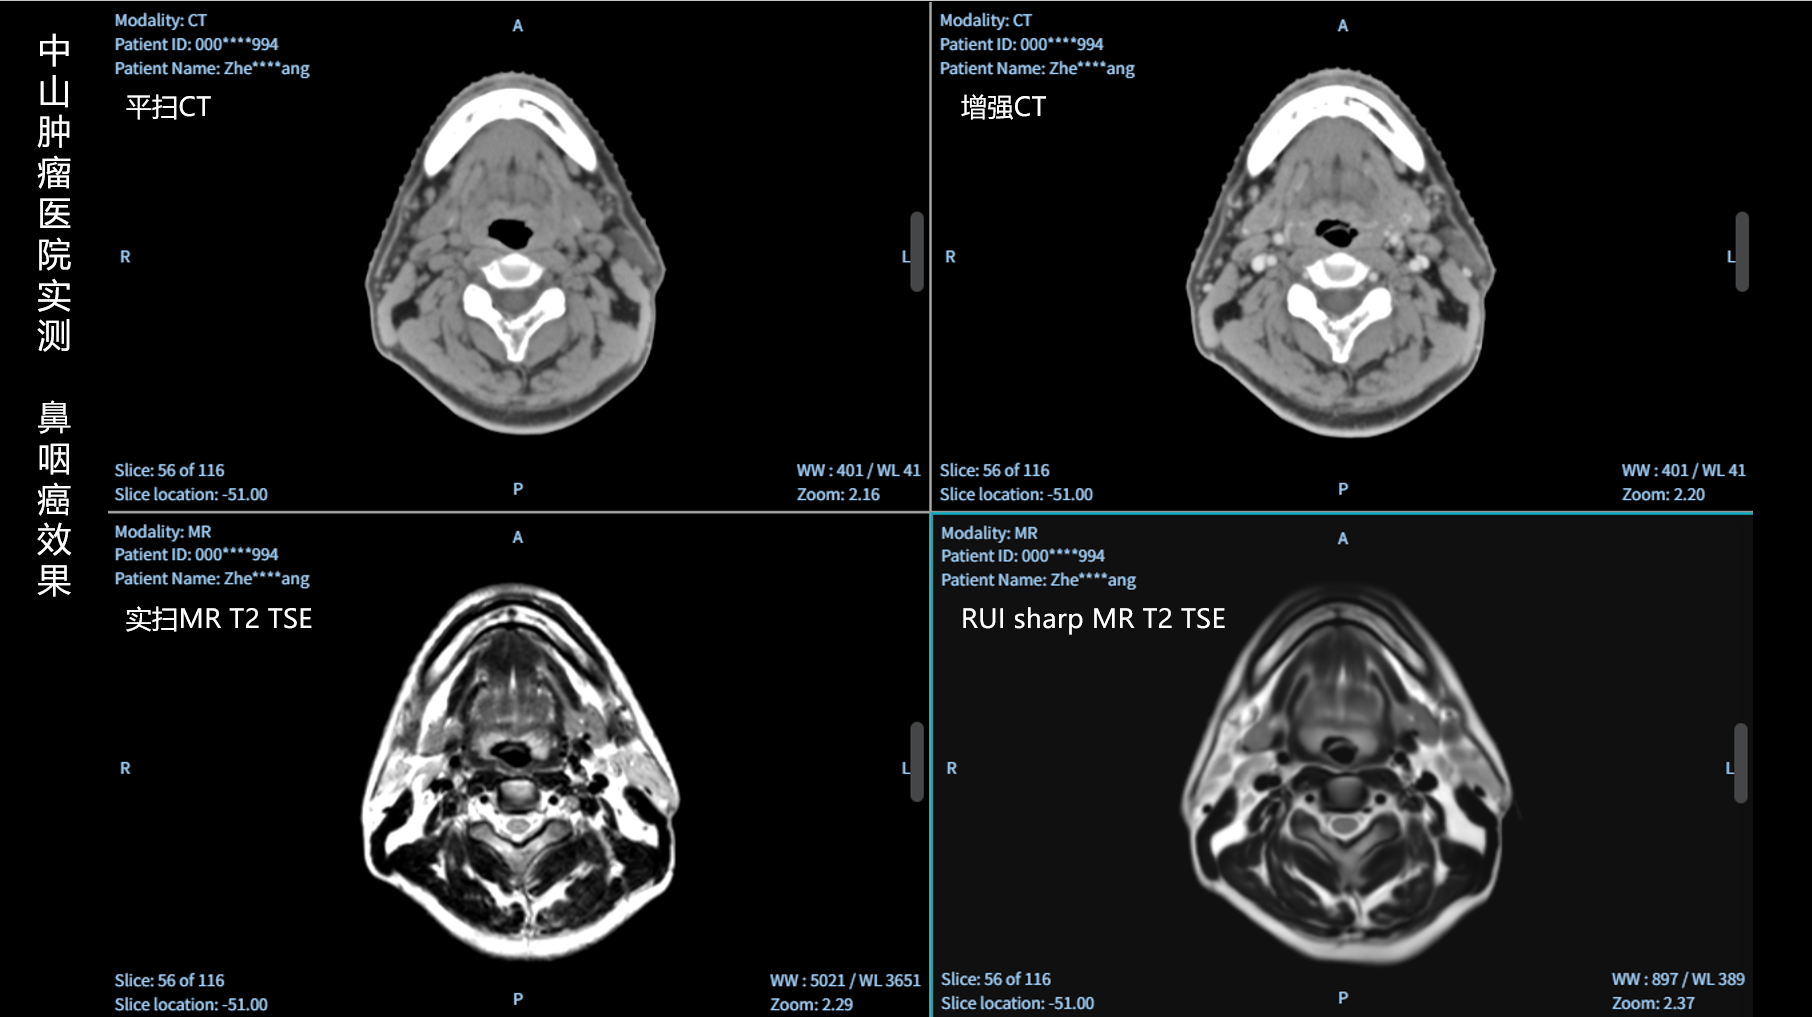

RUI sharp H(锐影)可在不依赖MRI的前提下,显著提升头部CT图像的软组织分辨率,为临床提供更高质量的辅助信息,尤其适用于MRI资源受限或较难配准的头颈部放疗感兴趣区勾画场景。

可大幅提高头部CT影像软组织分辨率,使肿瘤和周边器官显示更清晰,为放疗靶区勾画提供参考。

无需图像配准,CT和锐影图像同源,可匹配、叠加、"淡入淡出"显示。

实测效果